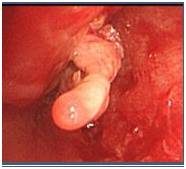

【病理表现】

还有一部分病例可表现为阻塞性支气管肺曲霉病,曲霉在气道管腔内呈团块状生长,导致支气管阻塞、扩张,病情进展迅速,随着病程发展可见肺实质内结节和空洞形成。

除少数典型者外,CT在曲霉菌支气管炎的诊断价值较差,经常需联合支气管镜检查并活检以进一步确诊。同时病变的预后主要依赖于基础疾病、机体免疫状况和诊断时机等因素,不完全取决于胸部CT的严重程度。

气道侵袭性曲霉病是一种少见的侵袭性曲霉病.其危险因素与IPA相似,临床表现和胸部影像学改变无特异性,故易漏诊或延迟诊断。内镜下表现有一定特征性,黏膜活检发现曲霉侵袭气道壁为确诊的依据。该病的全身治疗同IPA,气道内治疗对改善气道阻塞及呼吸困难十分重要。总体而言,该病预后不佳,宿主因素是决定预后的重要因素。